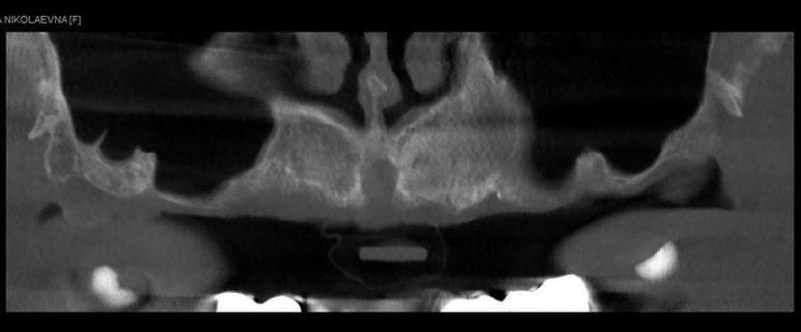

Дефицит кости по ширине. Качество костной ткани - D3-D4. Выраженная пневматизация верхнечелюстной пазухи.

Для симуляции хирургического этапа в программе RealGuide напечатана модель. Отмечены целевые точки платформ и апексов имплантатов, произведено пробное сверление, расстановка имплантатов для уточнения длины.

Установлены имплантаты диаметром 3,5, длиной от 9,5 до 14 мм. Достигнута бикортикальная фиксация. После установки имплантатов зафиксированы мультиюниты (L).